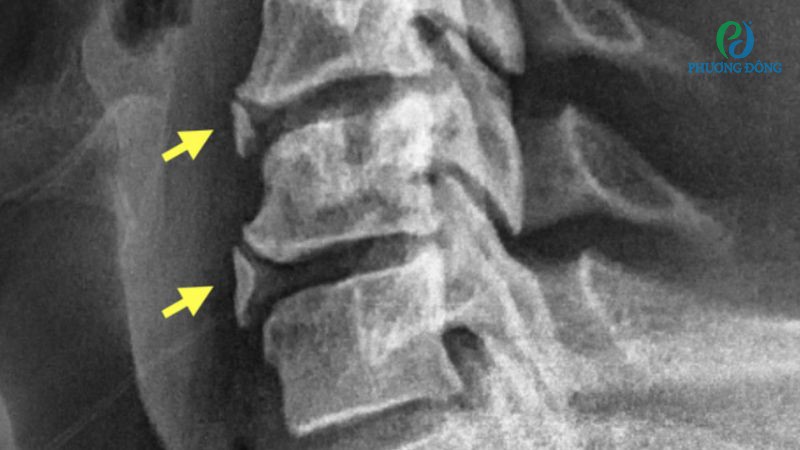

Trước khi tìm hiểu gai cột sống có chữa được không, bệnh nhân cần hiểu gai cột sống là gì? Gai cột sống hay thoái hóa cột sống là những phần xương phát triển thêm ở trên đốt sống, đĩa sụn hoặc dây chằng quanh khớp. Tình trạng này thường xuất hiện ở bệnh nhân viêm khớp cột sống, chấn thương hoặc sự tích tụ calci ở các dây chằng, gân.

Gai cột sống là thuật ngữ chỉ phần xương phát triển thêm trên đốt sống

Gai cột sống cổ và gai cột sống thắt lưng là hai thể bệnh thường gặp nhất, tác động tiêu cực đến chất lượng đời sống thường nhật như đau cổ, vai và gáy. Trong trường hợp trì hoãn, cơn đau do gai xương có thể lan xuống cánh tay, hai chân, làm hạn chế phạm vi vận động.